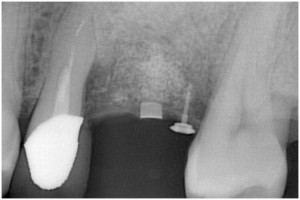

インプラント埋入直前

被せ物装着後